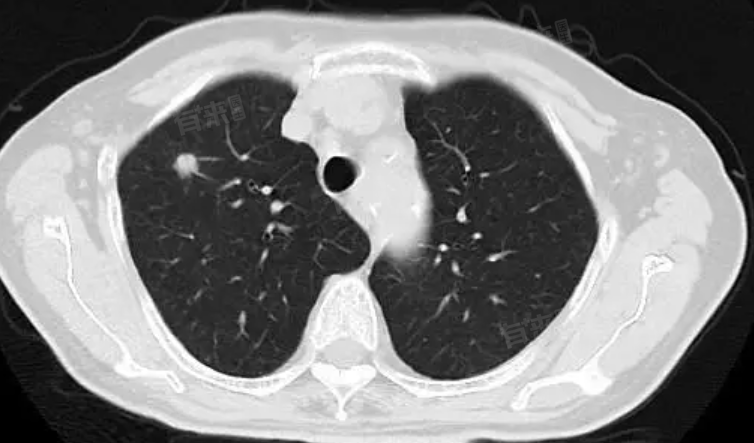

右肺小结节影是指在胸部影像学检查中发现的右肺内直径较小的圆形或类圆形的阴影。右肺小结节影产生原因多样,包括外伤或出血后修复、感染、自身免疫性疾病、肿瘤等。